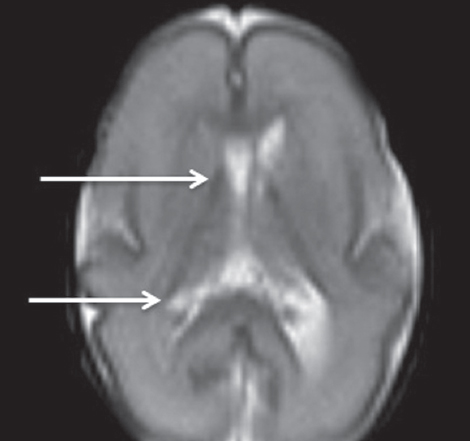

Как видно из таблицы, при выполнении МР-исследования в ПКВ 27–32 недели герминальный матрикс визуализировался у восьми недоношенных детей на ДВИ в виде усиления МР-сигнала вдоль боковых стенок боковых желудочков мозга, а также вдоль передних рогов над хвостатыми ядрами с обеих сторон (рис. 4). На Т2 ВИ герминальный матрикс достоверно выявлен у семи новорожденных (рис. 5). На Т1 ВИ герминальный матрикс достоверно выявлен у двух новорожденных (рис. 6). На последовательностях FLAIR герминальный матрикс не визуализировался.

Рис. 4. МРТ головного мозга недоношенного ребенка (ПКВ 28 недель), ДВИ, аксиальная проекция. Визуализируется гиперинтенсивный МР-сигнал от герминального матрикса в проекции наружных отделов боковых желудочков (отмечен стрелками)

Fig. 4. MRI of preterm newborn (PCA 28 wks.), DWI, axial plane. Hyperintensive MR-signal from the germinal matrix in the projection of the external parts of lateral ventricles (marked by arrows)

В нашем исследовании герминальный матрикс визуализировался на Т1-импульсной последовательности только у небольшого числа детей (у двух детей) в возрастной группе до 32 недель ПКВ в виде гиперинтенсивного сигнала от нижней стенки переднего отдела боковых желудочков. На Т2 ВИ герминальный матрикс выявляется у большего числа детей (у 7 из 9 детей) в возрастной группе 27–32 недели ПКВ, изменение интенсивности сигнала от герминального матрикса представлено гипоинтенсивным МР-сигналом от передних отделов и наружных стенок тел боковых желудочков. Использовать Т2-импульсную последовательность в оценке церебральной зрелости у недоношенных детей рекомендует S. Counsell [4]. Он отмечает снижение интенсивности Т2-сигнала от латеральных стенок и передних отделов боковых желудочков у недоношенных детей в ПКВ до 32 недель. Как полагает S.J. Counsell, сохранение гипоинтенсивного Т2-сигнала от этих структур у недоношенных детей старше 32 недель ПКВ может свидетельствовать о нарушении глиальной миграции [5].

На ДВИ субэпендимальный герминальный матрикс выявляется у подавляющего числа недоношенных детей в возрастной группе 27–32 недели ПКВ, у двух недоношенных детей — в возрастной группе 33–34 недели ПКВ. Герминальный матрикс на ДВИ-последовательности визуализируется в виде локального гиперинтенсивного сигнала в области передних отделов боковых желудочков и гиперинтенсивного линейного сигнала в области наружного края боковых желудочков (частично повторяющего контур наружной стенки желудочка). Чувствительность ДВИ в визуализации герминального матрикса превышает другие импульсные последовательности МР и позволяет получить более полную визуализационную картину регрессии субэпендимального герминального матрикса в вентрикулярных зонах головного мозга недоношенных детей.